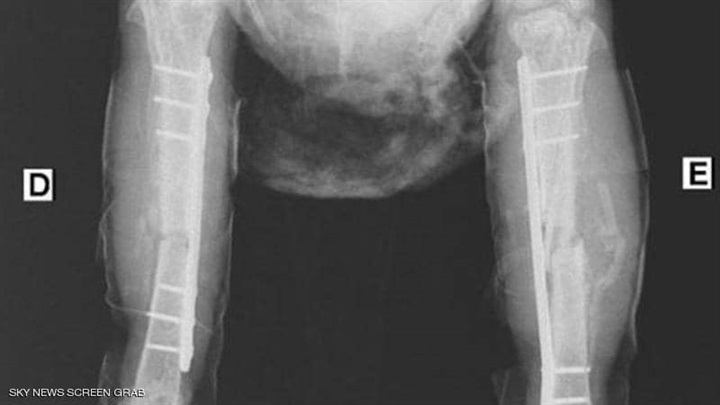

ونشر الطبيب البرازيلي عددًا من الصور للدجاجة بعد تضميد قدميها فضلاً عن الفحوصات الخاصة بحالتها الصحية، لتوضيح مدى صعوبة العمليات التي أجراها.

وتابع أرودا: "أجريت العملية الأولى للدجاجة في 2 سبتمبر الجاري، ثم عملية ثانية بعدها بيومين، لوضع "شرائح مسامير" لمعالجة الكسور الموجودة، وهي الآن في حالة مستقرة، لكن عملية الشفاء تحتاج إلى مزيد من الوقت.

واستكمل "أرودا" تصريحاته، إلى أن تكاليف العلاج وصلت إلى 200 دولار لكل ساق، مشددًا على أن الربح المادي لم يكن هو الأولوية لديه وفريقه خلال إجراء العمليتين، وكل ما يرغبوا به هو إنقاذ الدجاجة بقدر الإمكان.